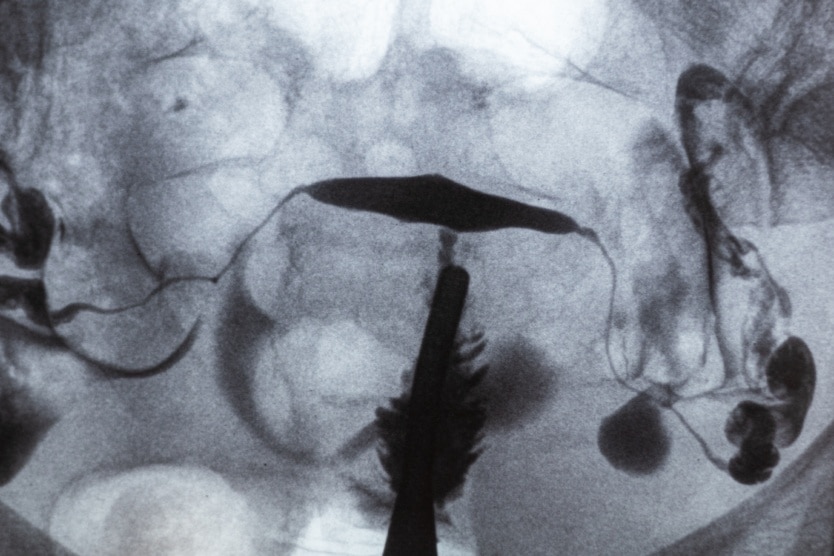

Peut-on faire une hystérosalpingographie avec ses règles ?

On vous a prescrit une hystérosalpingographie et vous vous demandez si cet examen est possible lorsque vous avez vos règles ? Faut-il le reporter si [...]